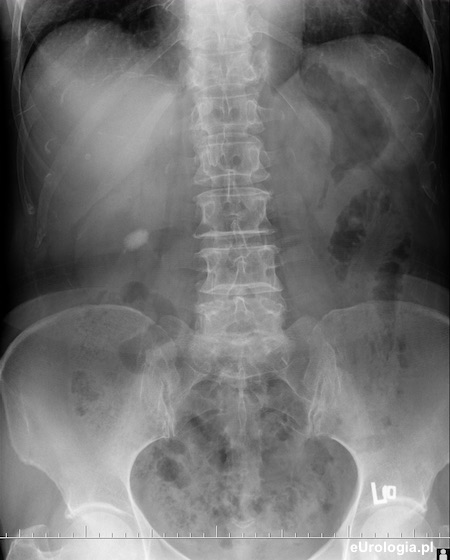

Urografia - kamica nerki prawej

Zdjęcie przeglądowe jamy brzusznej w pozycji leżącej - cień wapienny w rzucie prawego pola nerkowego o wymiarach 20x10 mm.